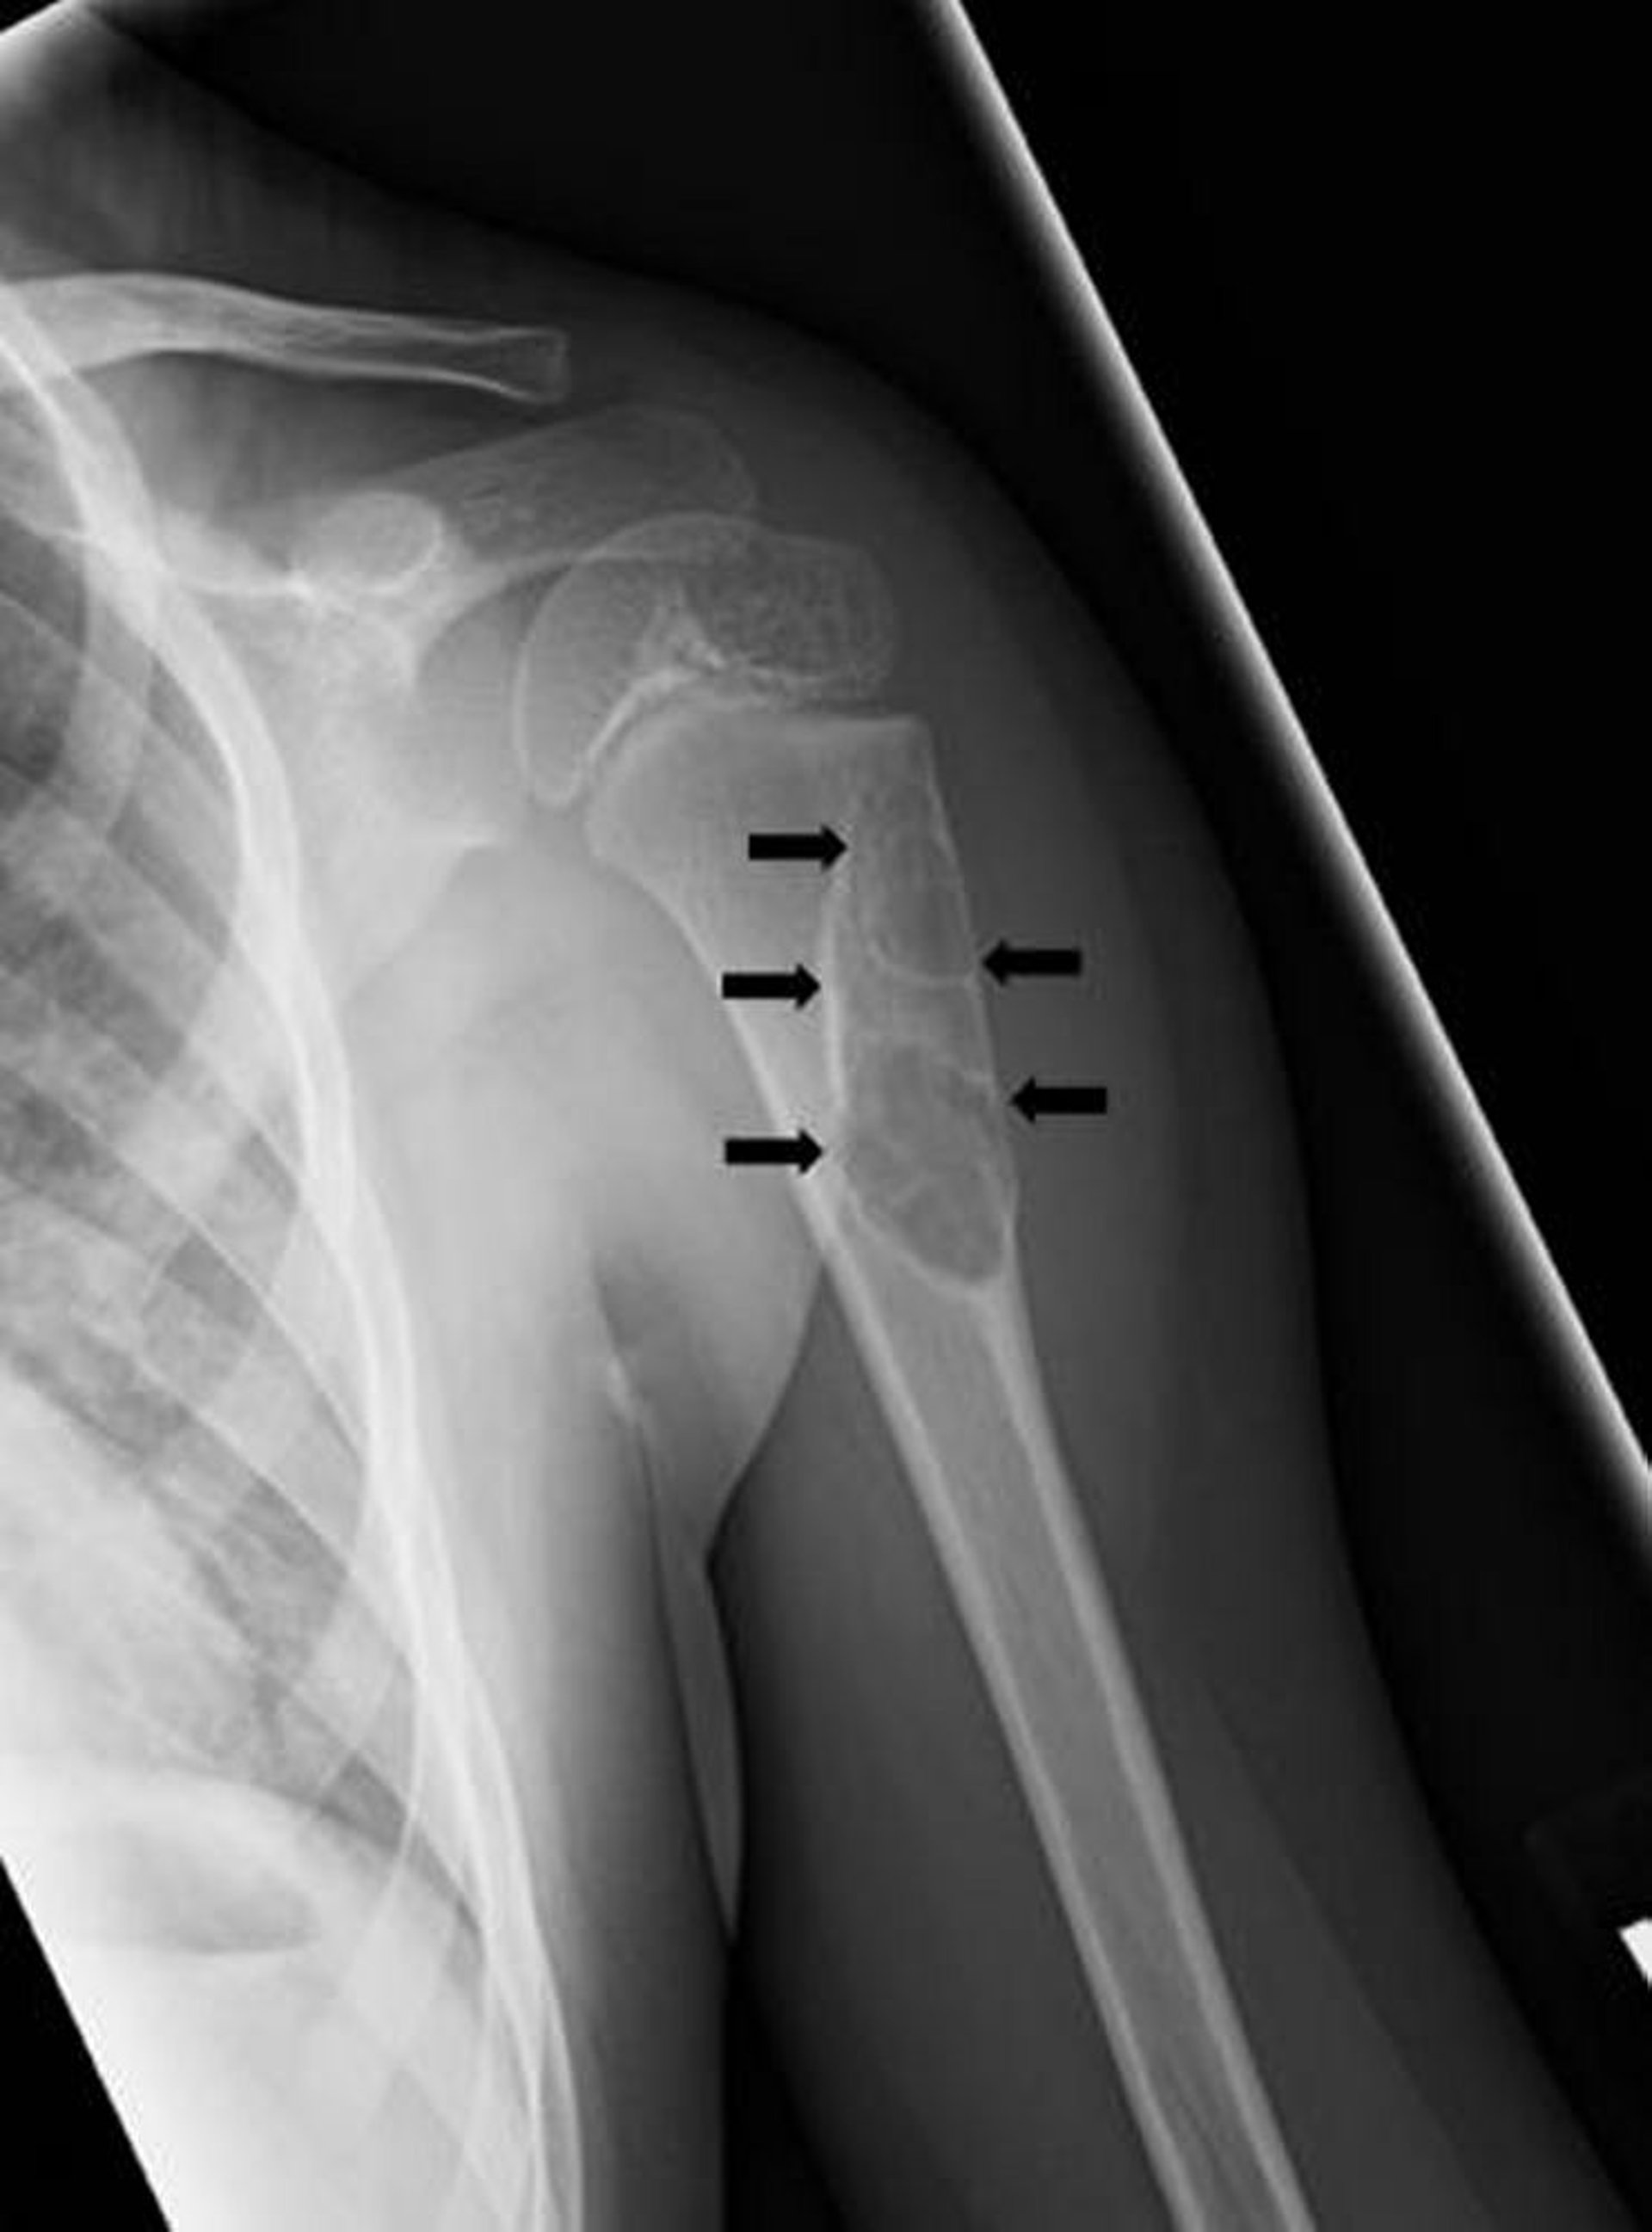

This radiograph shows a cystic lesion (arrows) of the humerus in child consistent with a unicameral bone cyst.

Image courtesy of Michael J. Joyce, MD, and Hakan Ilaslan, MD.